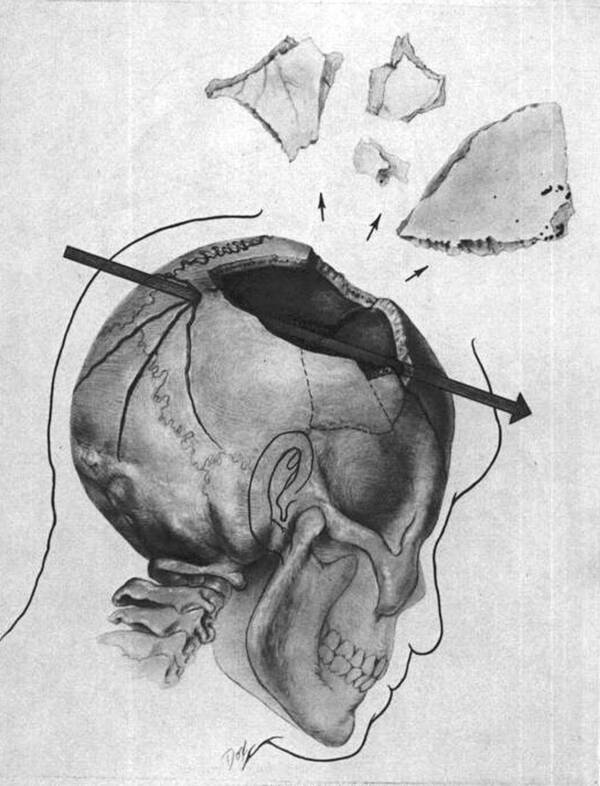

Public DomainA diagram provided to Congress which shows how one of the bullets passed through JFK ’s brain .

Public DomainA diagram provided to Congress which shows how one of the bullets passed through JFK’s brain.